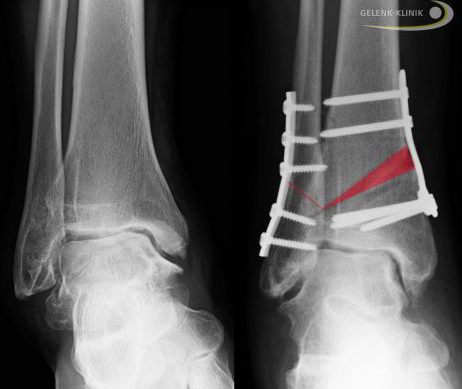

Schienbeinumstellung bei Hohlfuß

Die operative Umstellung des Schienbeins über dem Sprunggelenk kann zur Entlastung des medialen Sprunggelenks notwendig werden. Der Hohlfuß muss dabei ebenfalls operativ korrigiert werden. Bei dieser Umstellung des Schienbeins handelt es sich um eine gelenkerhaltende Operation am Sprunggelenk.

Wir wollen den Schaden am oberen Sprunggelenk möglichst aufhalten, bevor durch die atypische Belastungslinie der bei Hohlfuß verdrehten Beinachse Gelenkverschleiß entsteht.